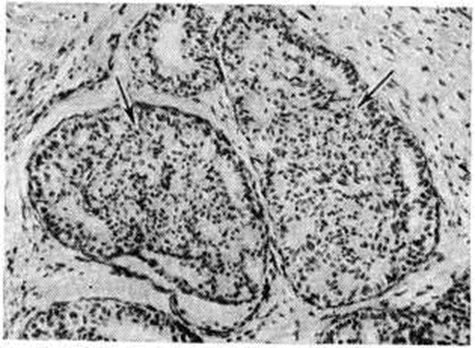

Исследование: микропрепарат молочной железы в медицине

Раздел: Снимки-откровения